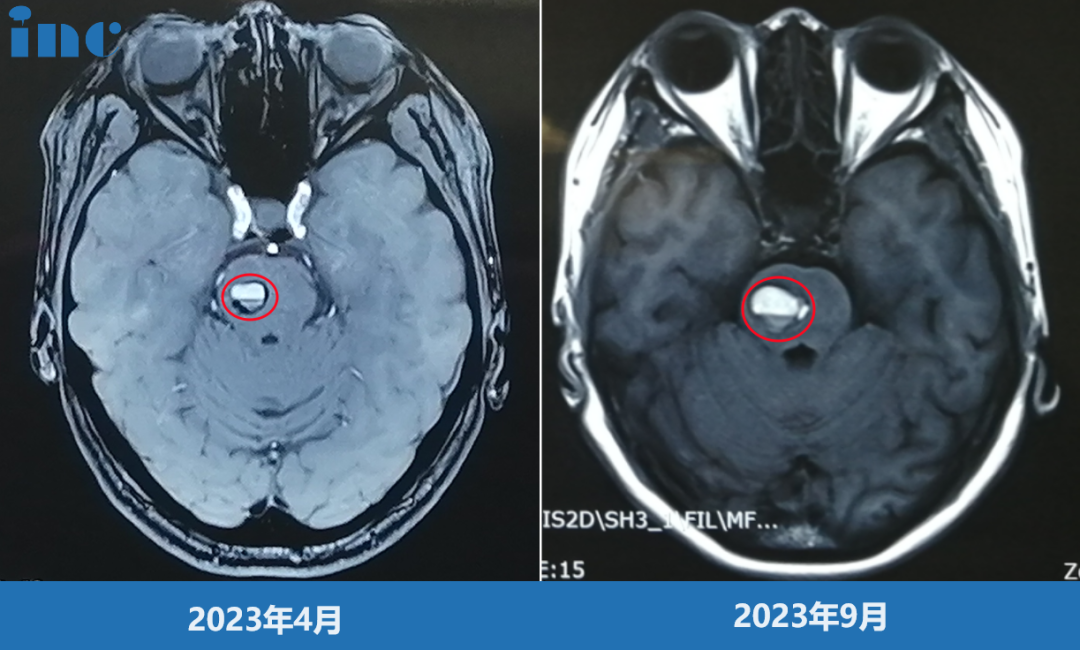

影像对比提示我的海绵状血管瘤增大,出血量逐渐增多

然而,这颗良性的海绵状血管瘤并不安分。随后的影像检查对比显示,它在两年内从最初的0.8cm长到了2.0cm,而且多次出血。出血的量和频率都在增加,间隔时间越来越短。我开始出现头晕、眼睛不自主跳动(眼肌痉挛)、耳朵不适等症状。